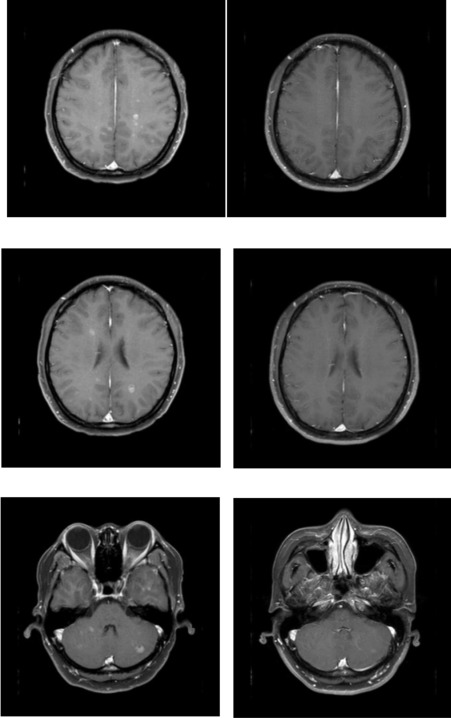

• 头颅MR(2025年10月18日):脑实质平扫增强未见明显异常。

乳腺cr是什么双优标杆!从PD到18 个月达颅内CR,瑞波西利改写32岁HR+/HER2-晚期乳腺癌患者命运_https://www.jmylbn.com_新闻资讯_第8张

图 2025年10月18日 头颅MR

②治疗18个月后,2025年10月18日颅脑MR对比2025年3月27日颅脑MR,患者脑转移灶消失,未见明显异常信号,达到CR,患者生活质量良好,药物耐受性好。

乳腺cr是什么双优标杆!从PD到18 个月达颅内CR,瑞波西利改写32岁HR+/HER2-晚期乳腺癌患者命运_https://www.jmylbn.com_新闻资讯_第10张

图 治疗18个月前(左列)后(右列)影像学疗效对比